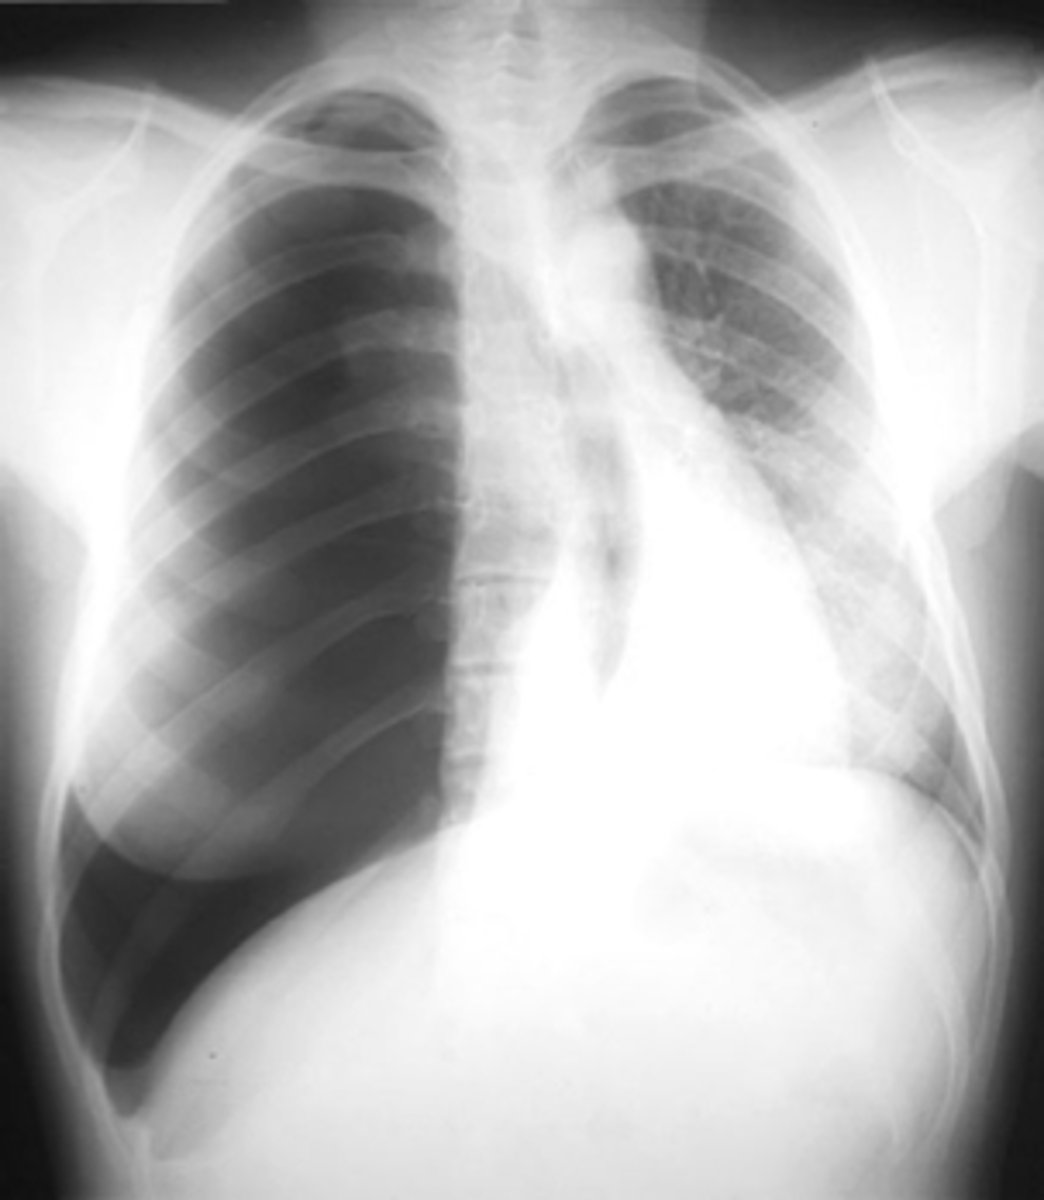

Right sided atelectasis

knowt flashcard image

Right sided non tension pneumothorax

Atelectasis (right)